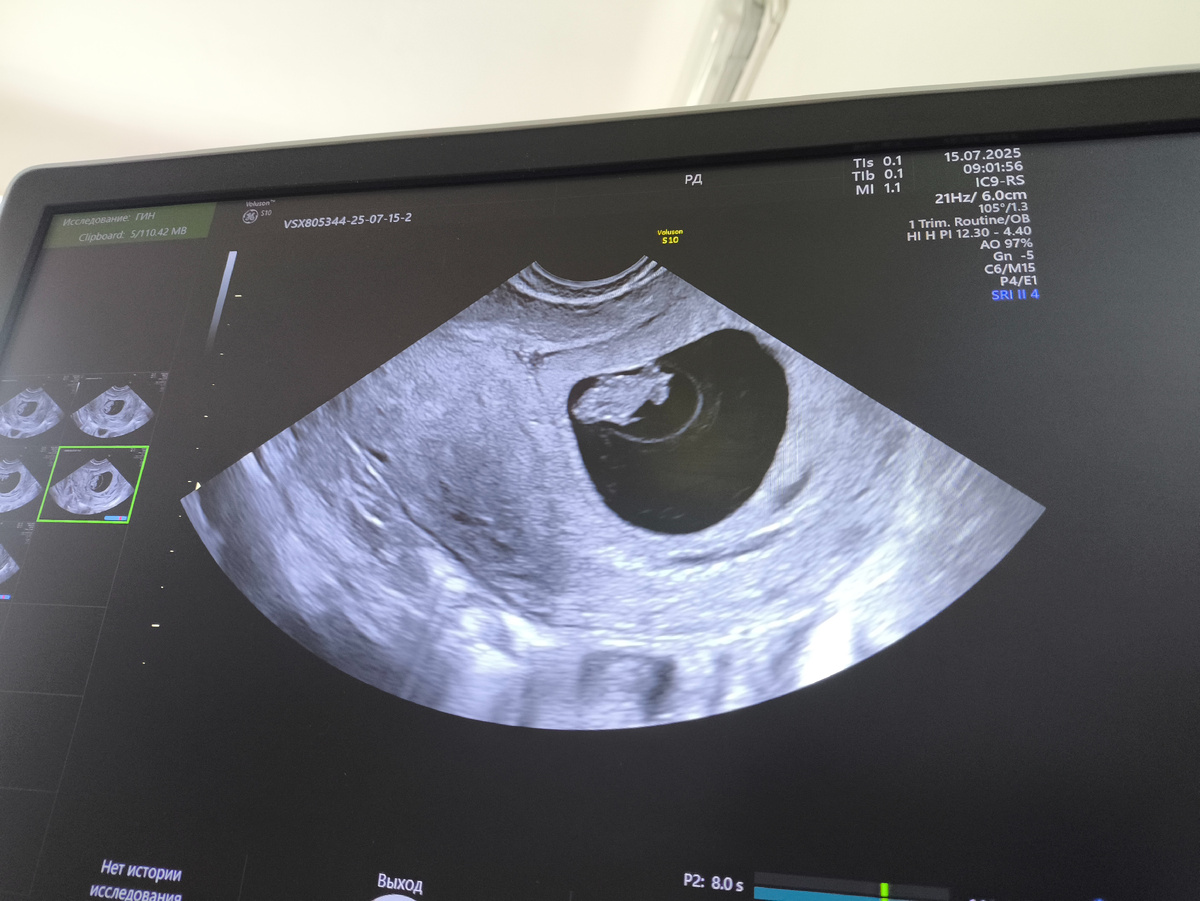

Скрининг в 12 недель. Двойня, многоплодная беременность, наступившая естественным путём, первая в 34 года, я и отец детей совершенно здоровы и без вредных привычек, у плодов одна плацента на двоих. Называется монохориальная диамниотическая двойня. Это близнецы, всегда один пол и одинаковая внешность.

Это 8 недель, как раз произошло раздвоение:

Затем на 12 недель во время скрининга обнаружили мегацестис у одного из двух плодов, при этом все остальные показатели полностью в норме. Направили на повторное УЗИ через пару дней уже к генетикам, там снова увидели мегацестис.